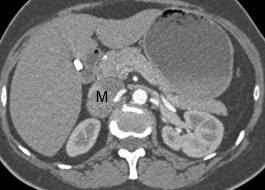

Фотографии опухоли медуллярной аденокарциномы

Раздел: Снимки-откровения